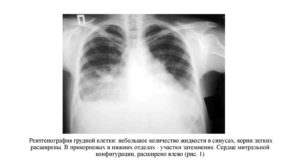

Примерная расшифровка рентгенограммы при пневмонии:

На рентгенограмме легких в прямой проекции визуализируется крупноочаговая инфильтративная тень S3 правого легкого. Корень справа уплотнены за счет инфильтрации; слева – без особенностей.

Контуры диафрагмы и реберно-диафрагмальные синусы без особенностей. Сердечная тень расширена в поперечнике влево. Заключение: рентген признаки правосторонней верхнедолевой пневмонии. Нельзя исключить туберкулезную инфильтрацию.

Рекомендовано: консультация фтизиатра.

Такие симптомы рентген показывает при наличии воспалительных процессов в легких (пневмония туберкулез) или разрастании соединительной ткани (фиброзное уплотнение корней).

На следующем этапе нужно оценить купола диафрагмы. Они могут быть приподняты или релаксированы (расслаблены из-за нарушения иннервации). Рядом с ними расположены реберно-диафрагмальные синусы. При наличии экссудативного плеврита в плевральных полостях отмечается скопление жидкости.